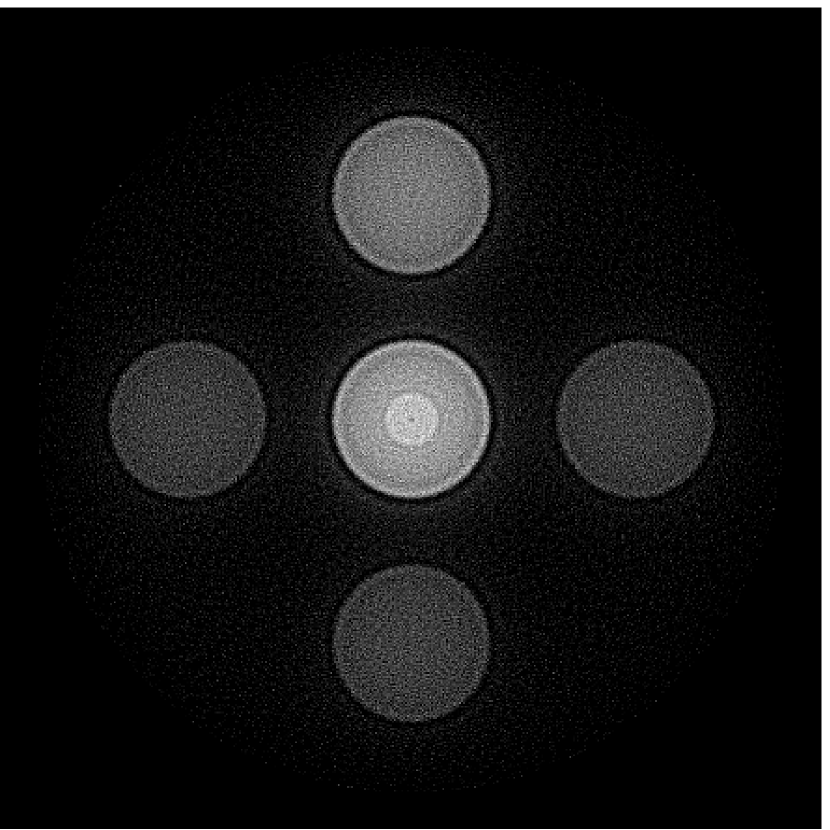

V-A3 Effect of data incompleteness

Incomplete, or sparsely sampled, data sets are sometimes acquired in practice. To study the effect of data incompleteness on the VP algorithm, we reconstructed images from data corresponding to half of the equally spaced transducers (). Because the data were noiseless, no explicit regularization was employed () in the conventional reconstruction algorithm. However, the explicit regularization was still employed in the VP algorithm because of the ill-posed nature of the joint reconstruction problem. The results are shown in Figure 5. As expected, use of the incomplete data set resulted in less accurate reconstructed images for both the conventional iterative reconstruction method and the VP algorithm. However, this effect was more pronounced for the VP algorithm. Note that for the VP algorithm, larger values of the regularization parameters were applied when the incomplete data set was employed than when the complete data set was employed (Figure 5(h) and 5(g)).